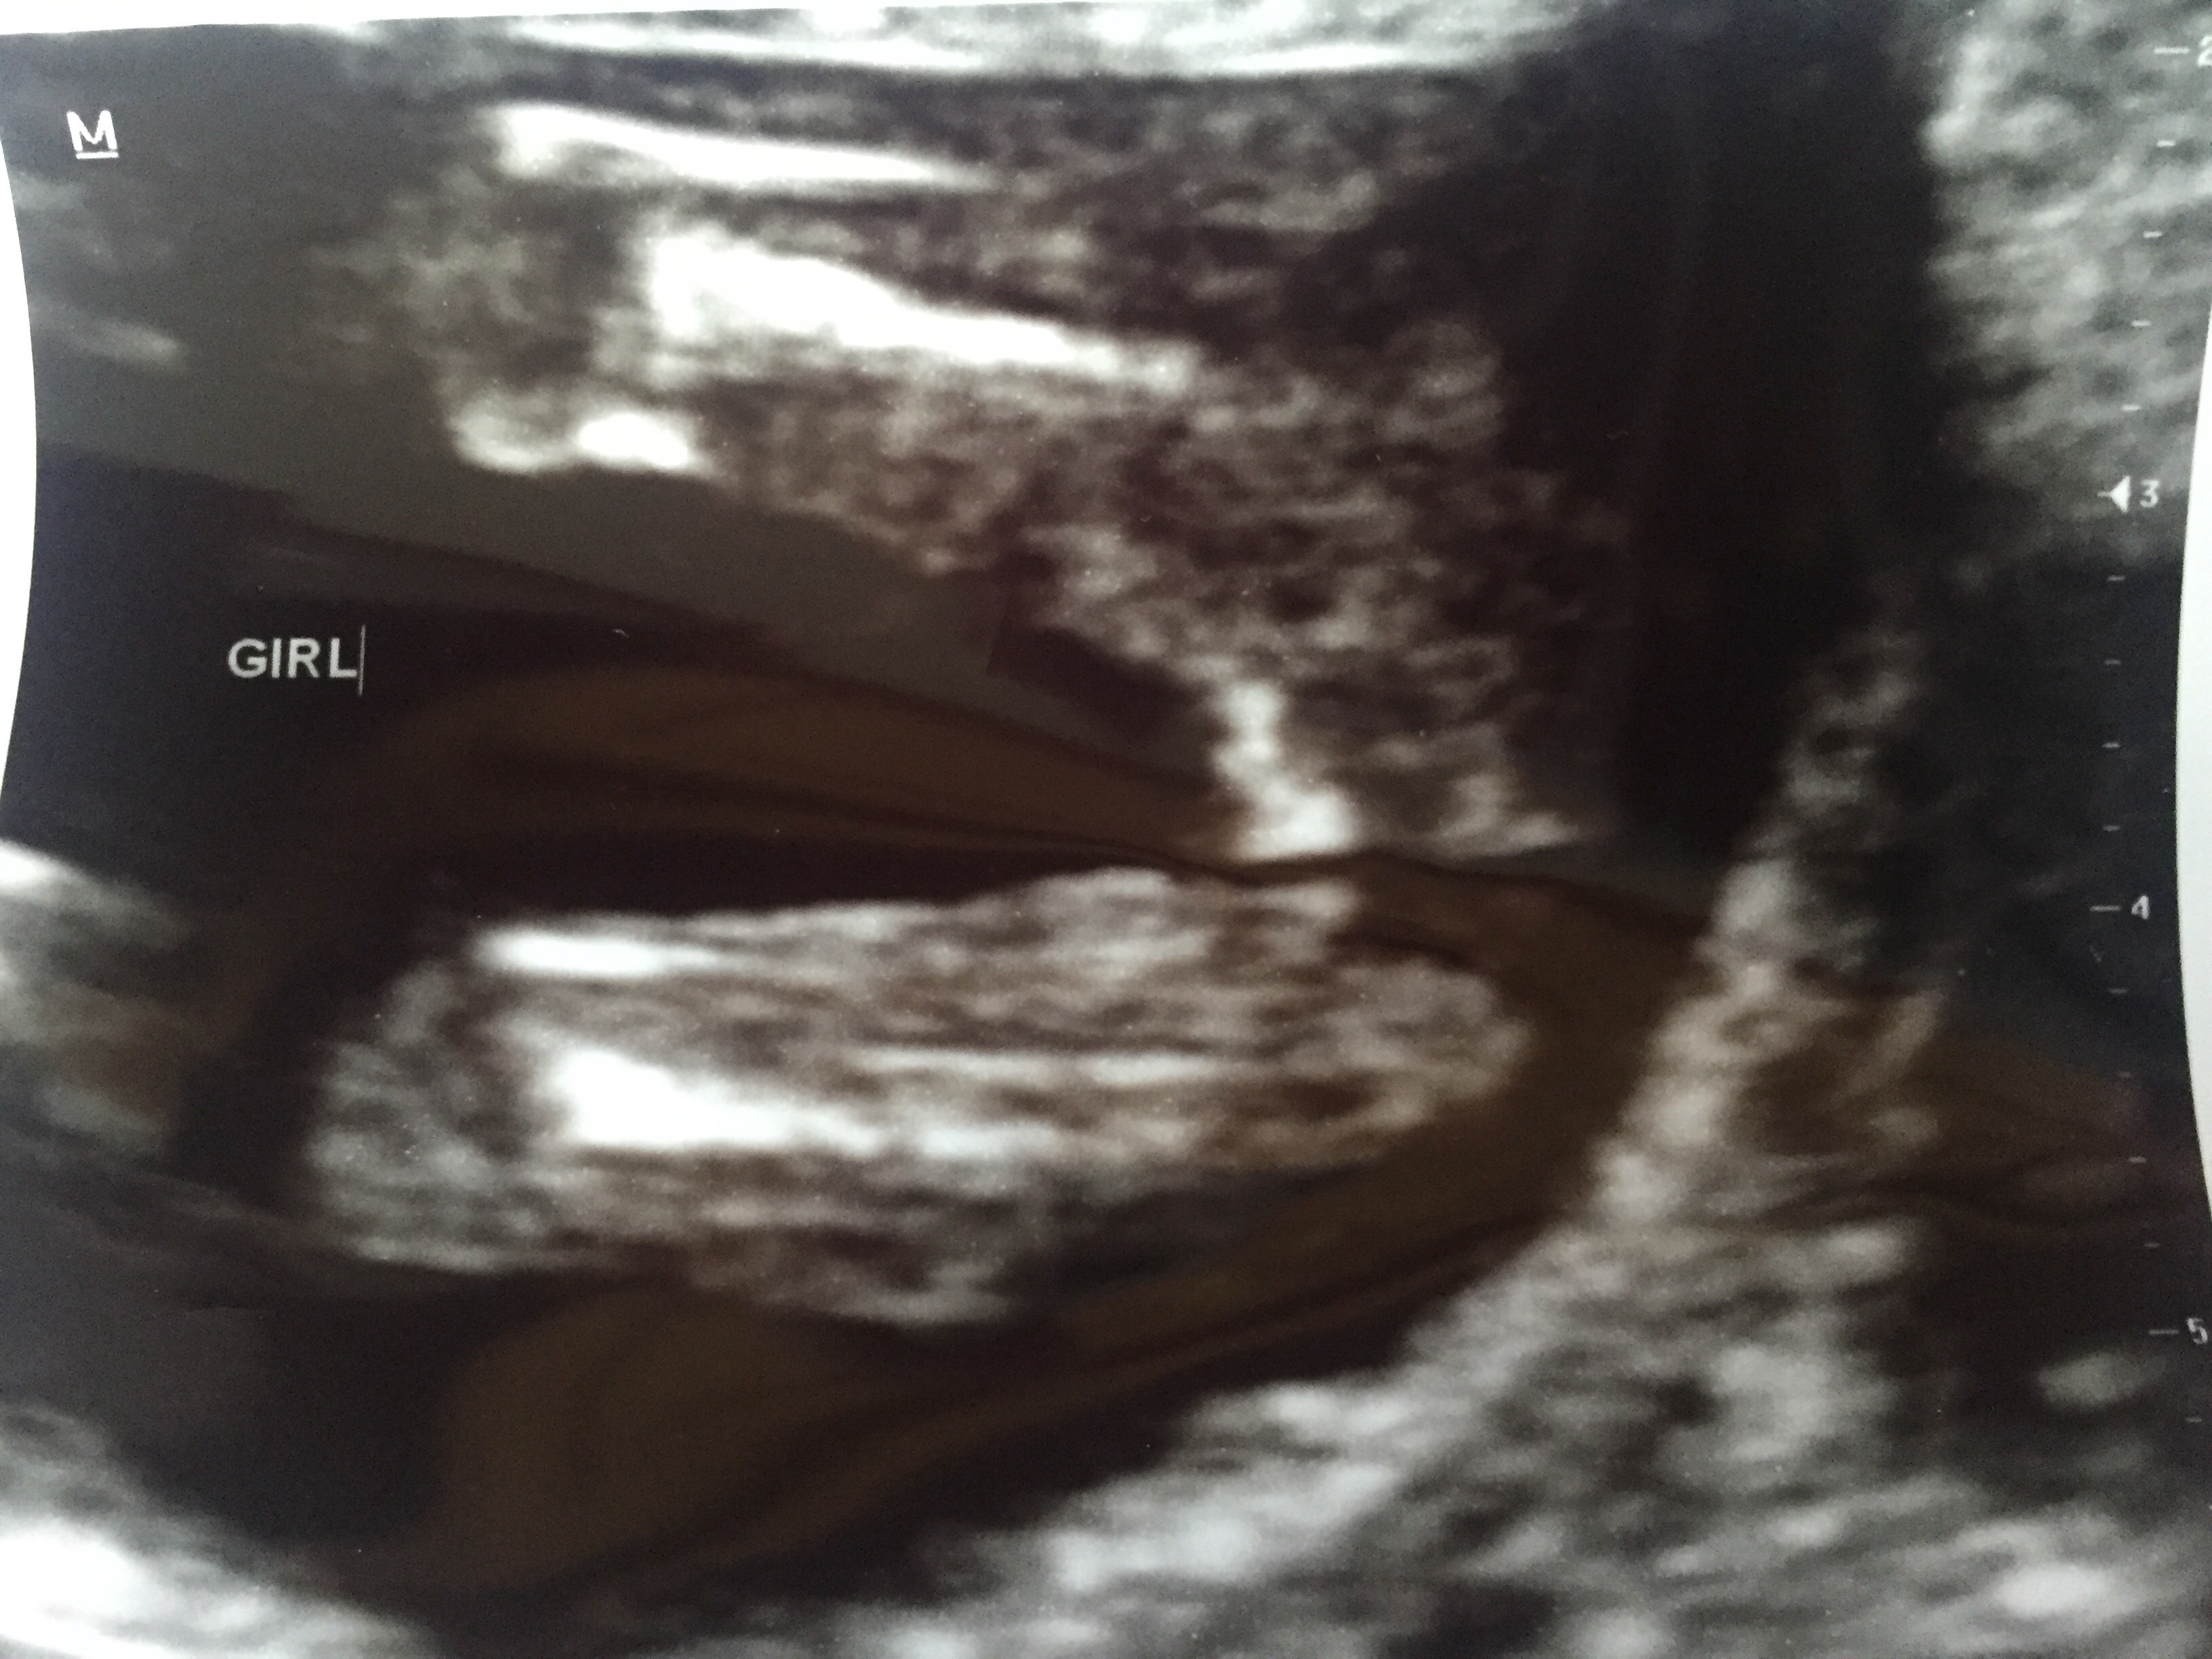

Hi Everyone! I had an ultrasound today at 15 weeks, 2 days. The tech told me I'm having a girl. Do y'all agree? I guess I need extra reassurance after two boys! :)

Looks pretty girly to me. Boys are normally quite obvious with something sticking out there!